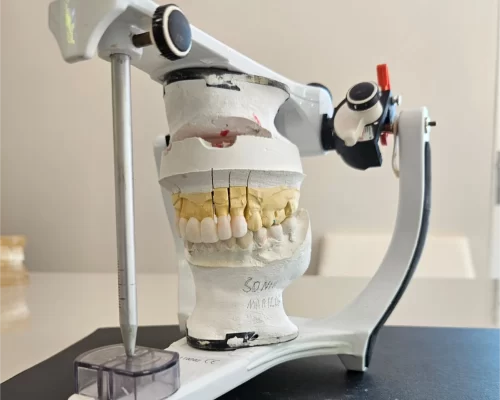

Implantes & Reabilitações Funcionais

Reabilitação oral planejada com implantes e próteses totalmente personalizadas.

Planejamento digital e câmera intraoral.

Você acompanha cada etapa da evolução do seu tratamento.

- Planejamentos digitais com previsibilidade e precisão

Planejamento do seu sorriso com encerramento e Mockup